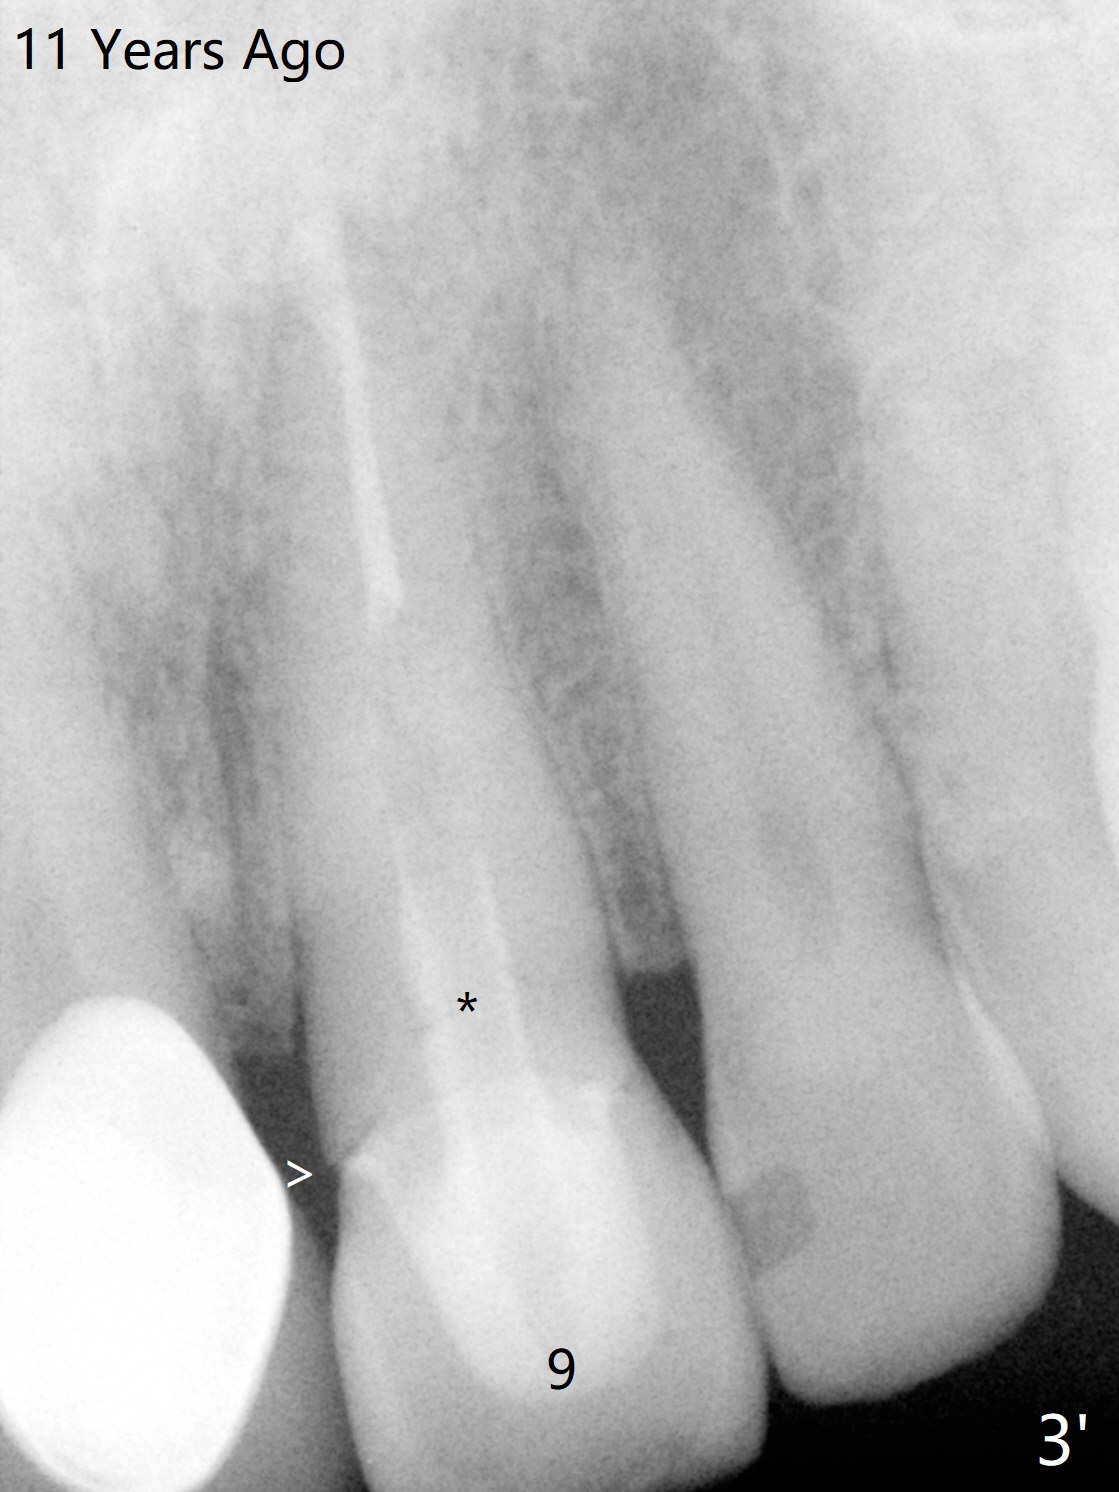

A 58-year-old man fractures the tooth #9 equigingival (Fig.1) and fiber post (Fig.2,3 *). The marginal gingiva is erythematous and edematous (Fig.1 *), suggesting biologic width violation. Redo crown would aggravate the issue. In addition, the mesiobuccal root of the tooth #14 has vertical fracture (Fig.4,5), evidence of heavy mastication. In fact the tooth #13 was also fractured apparently due to heavy occlusion before extraction. It is the best to extract the tooth #9 for implant (Fig.6), or tissue-level (3.5x14 or 17 mm).